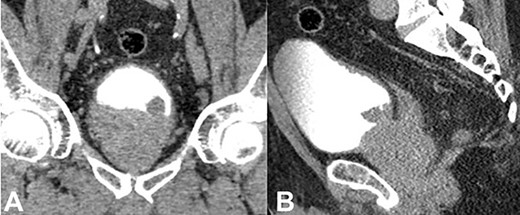

He underwent a bone single-photon emission computed tomography (SPECT) scan, which showed a focus of uptake suspicious for a left pubic tubercle metastasis, as well an area of focus in the left posterolateral side of the bladder. He later underwent a complete staging Computed tomography (CT) scan of the chest, abdomen and pelvis (Fig. 1A, B), which demonstrated prostatic enlargement, a mixed sclerotic lesion on the left pubis in keeping with metastatic disease, a polypoid mass on the left side of the bladder, highly suspicious for a primary bladder tumour, and left external iliac lymph nodes, the largest measuring 16 mm. Based on the above findings, the patient had a flexible cystoscopy that revealed an enlarged occlusive prostate, and a calcified lesion at the bladder neck of possible prostatic or bladder origin. Urine cytology was not sent at the time.